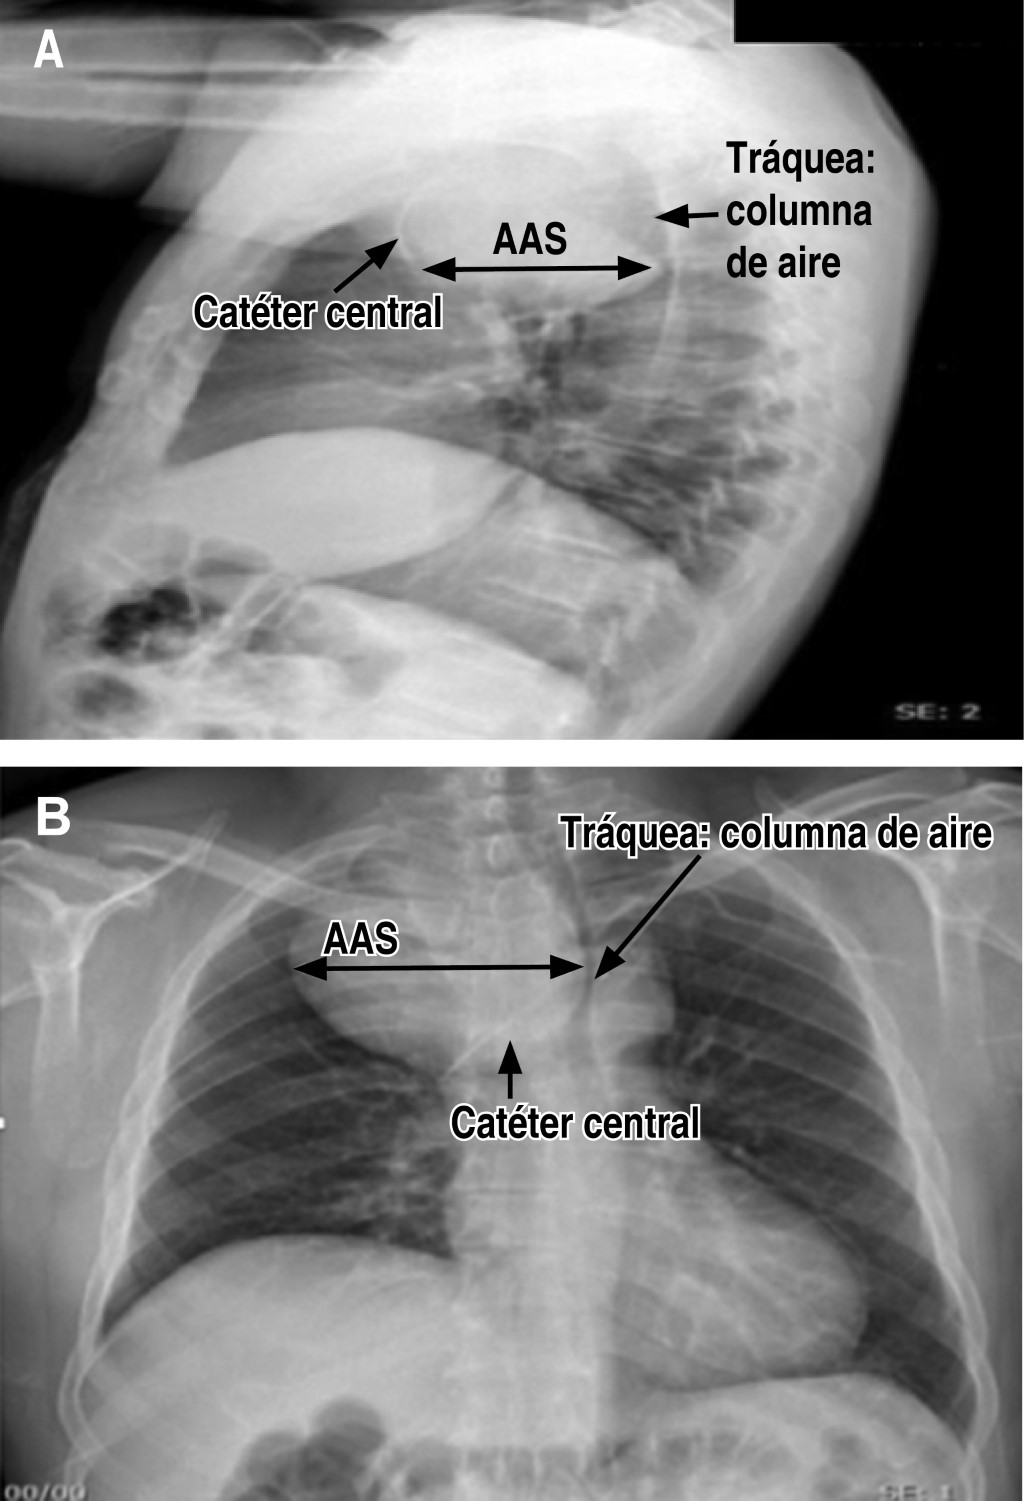

Sedoanalgesia with ketodex for selective intubation in the resection of a giant aneurysm of the subclavian artery associated. Case report

A giant subclavian artery aneurysm associated with superior vena cava syndrome occurs infrequently. Complexity of the approach will depend on the size, shape, and position of the aneurysm, particularly when a potential collapse of the airway is expected due to the compressive effect of the mediastinal mass after using neuromuscular relaxant for airway approach. We present a case in a 57-year-old male with shortness of breath in dorsal that increases with left lateral decubitus during five years of evolution. Radiological studies reported giant mediastinal mass compatible with an aneurysm of the right subclavian artery, which produces critical compression and airway displacement, particularly in trachea at level of the carina. The patient is scheduled for resection of the aneurysm and requires selective intubation for isolation of the right lung during surgery which was performed with the awake patient technique using sedoanalgesia with ketodex. The objective of the case is to share the experience using ketodex as an alternative for the tolerance of procedures that requires the cooperation of the patient where propofol and neuromuscular relaxant may be a problem for airway permeability and approach.

Figure 1